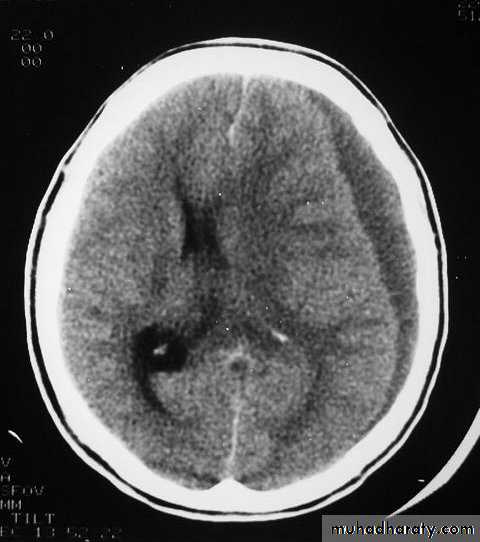

CT scans demonstrates contusions as small areas of haemorrhage in the cerebral parenchyma.

3. Cerebral Contusion